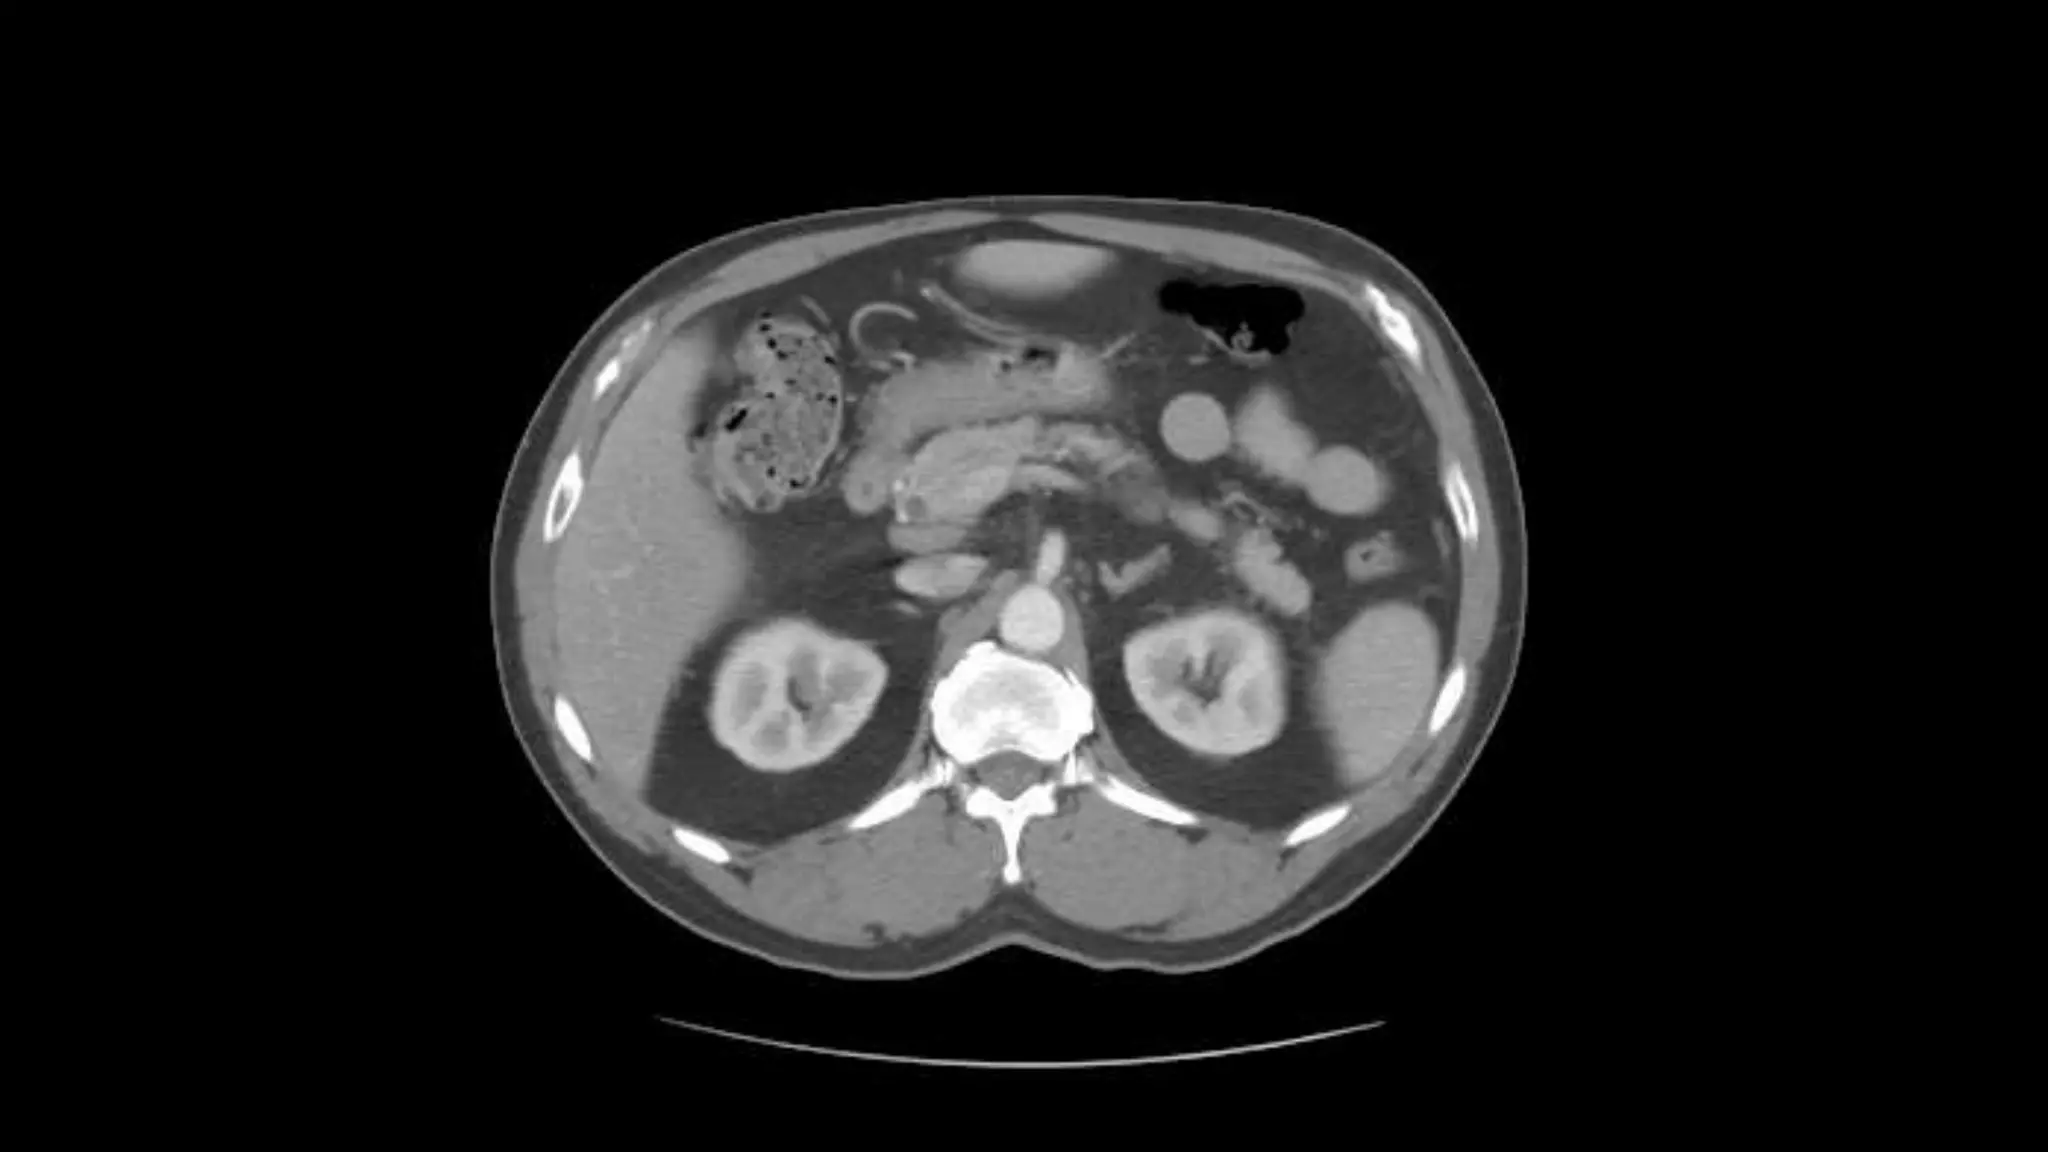

Pancreas

This is the Superior Mesenteric Artery branching

off the Aorta.

Rt. and Lt.Kidneys